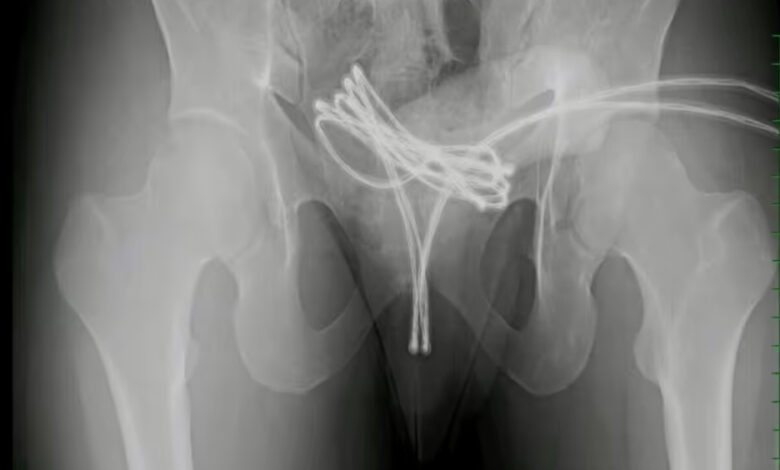

Las radiografías revelaron que el cable estaba doblado dentro de su cuerpo, con un extremo sobresaliendo de la uretra.Los intentos manuales para retirar el cable fueron infructuosos.

Por ello, los médicos de la Facultad de Medicina de la Universidad Drexel de Pensilvania procedieron a una intervención quirúrgica bajo anestesia general.

Utilizaron un ureteroscopio, una cámara endoscópica, que se insertó junto al cable para guiar la extracción y evitar daños adicionales.

Bajo visión directa, los médicos lograron tirar suavemente del cable a través de la uretra. Para completar la extracción de manera segura, fue necesario cortar el cable con tijeras resistentes.Tras el procedimiento, se encontraron solo traumatismos internos menores.